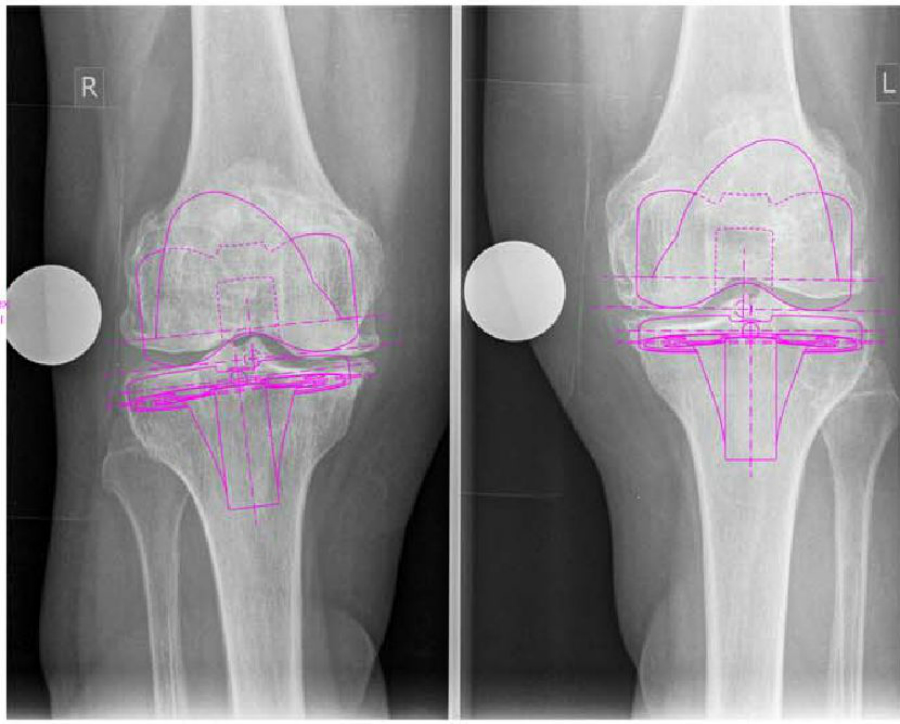

Совместно с ведущими специалистами Финской Клиники Кокса произведены операции по эндопротезированию тазобедренных и коленных суставов, а также ревизии суставов, которые представляют собой операции по репротезированию протезированных ранее и пришедших в негодность, а также осложненных суставов. Такого типа операции впервые в Армении были проведены в Армяно-Финской клинике Кокса-Наири. Несмотря на совершенно одинаковое с Финской клиникой качество и уровень оперативного вмешательства, оно значительно доступнее для пациентов в плане стоимости и комфорта.

Эндопротезирование сустава - это операция по замене компонентов сустава имплантантами, которые имеют анатомическую форму здорового сустава и позволяют выполнять весь объём движений. Целью эндопротезирования сустава является уменьшение болевого синдрома и восстановление функции сустава. Замена сустава – эффективный, а порой и единственный способ восстановления его функции, сустава, позволяющий значительно улучшить качество жизни. После подобных операций пациент забывает о болях в суставах и возвращается к активной жизни.

Для эндопротезирования в центре используются протезы лидирующих фирм производителей эндопротезов. Каждый протез проходит многоступеньчатый контроль и имеет сертификацию.

До операции проводится тщательное обследование пациента, во время которого определяются показания и противопоказания к проведению хирургического вмешательства, а также производят тщательный замер и подбор необходимого протеза. Чаще всего операции по эндопротезированию суставов проходят без серьезных осложнений и позволяют практически во всех случаях добиться восстановления двигательной активности пациента, а также избавить его от многолетней боли.